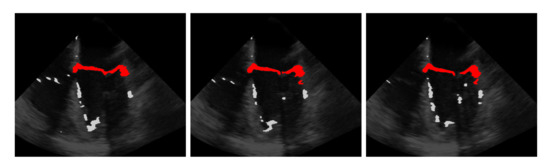

5.5. Results on the EchoNet-Dynamic Dataset